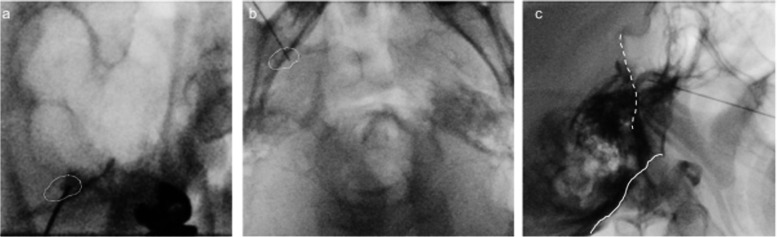

Case presentation: A 49-year-old male with multiple sclerosis exhibited persistent dull pain and paroxysmal electric shock-like pain in his bilateral maxillary molars and mandible. He was diagnosed with trigeminal neuralgia due to multiple sclerosis. Due to severe side effects, it was difficult to achieve adequate pain control with medication alone. By performing low-temperature radiofrequency thermocoagulation and pulsed radiofrequency of the Gasserian ganglion while monitoring masseter muscle contraction, a satisfactory and rapid analgesic effect was obtained without masticatory atonia.